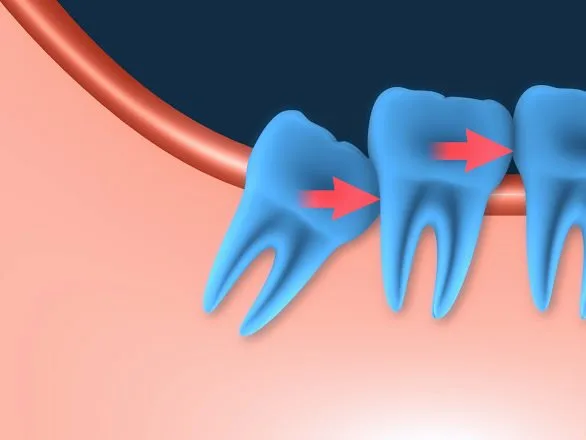

Além disso, a técnica previne a reabsorção óssea, mantendo a estrutura do osso e a estética do sorriso. Nossa equipe realiza uma análise detalhada de cada caso, assegurando que o paciente esteja apto para o método.

Outro ponto importante é a preservação do osso. A técnica evita a reabsorção óssea, mantendo a estrutura facial e garantindo resultados duradouros. Com um planejamento cuidadoso, o procedimento oferece segurança e eficiência.

Entre as complicações associadas à técnica, destacam-se infecções e a rejeição do implante. Pacientes com infecções ativas ou insuficiência óssea podem não ser indicados para esse método. A falta de osso suficiente pode comprometer a estabilidade do dente e aumentar os riscos de falha.

A carga imediata também se destaca pela estabilidade. A técnica promove uma integração óssea mais rápida e segura, preservando a estrutura do osso e garantindo resultados duradouros. Isso é especialmente importante para pacientes que desejam evitar a reabsorção óssea.

O candidato ideal para a carga imediata deve ter uma boa saúde bucal e estrutura óssea adequada. Pacientes com infecções ativas ou insuficiência óssea podem não ser indicados para esse método.